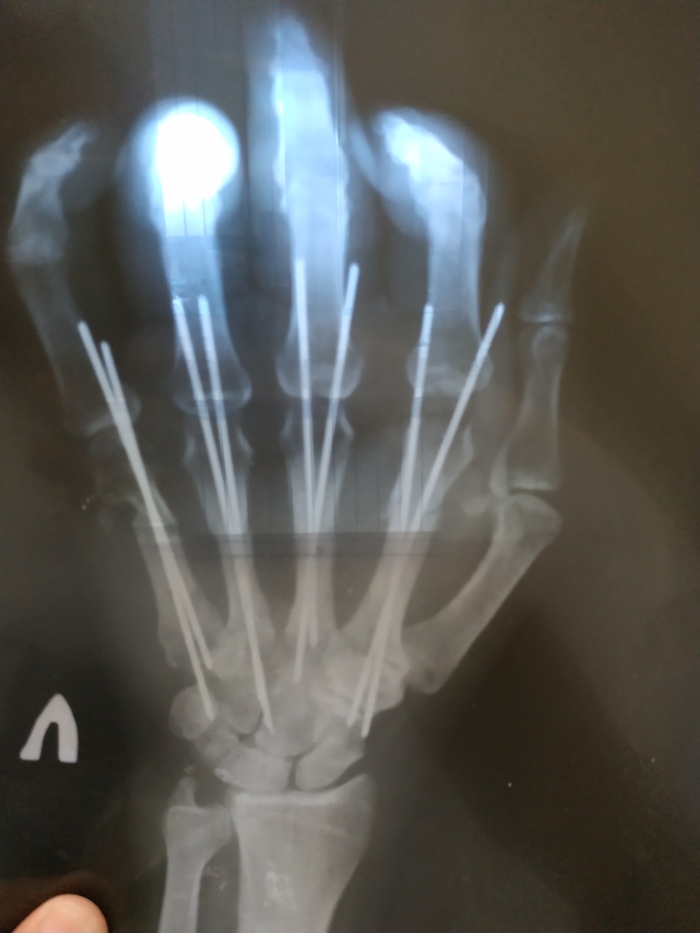

Не суй руку в погрузчик...

Или в продолжение истории https://pikabu.ru/story/kogda_ne_soblyudaesh_tekhniku_bezopa... . Через 2 месяца. Убран гипс и направляющие.

Ещё раз - берегите себя.